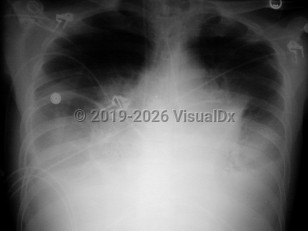

Chest pain, Pleural effusion, 50-59 year old Female

Congestive heart failureCongestive heart failure

Pulmonary edema

Dilated cardiomyopathyDilated cardiomyopathy

Pericardial effusionPericardial effusion